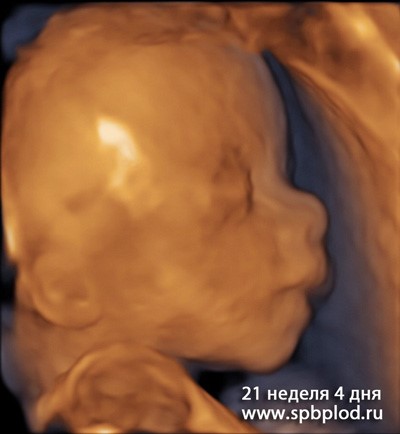

УЗИ пплода в 21 неделю и 4 дня в режиме 3D

3D УЗИ пплода в 21 неделю и 4 дня